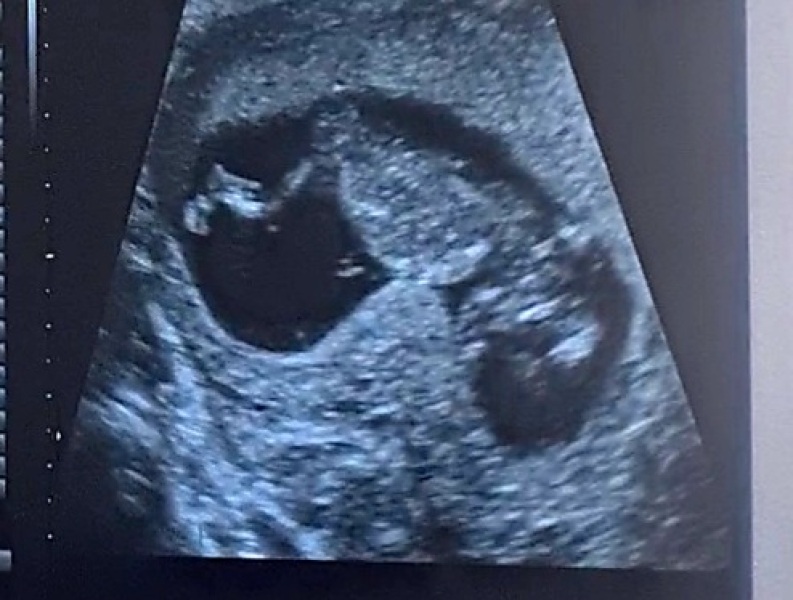

Went for the 12 week scan today ❤️ put me back a few days so I’m 11w4d, but baby was perfectly healthy and happy, all snuggled up and waving at us 🥹 was such a relief to see it, I’ve felt anxious the last week or so about whether something could have happened since our private scan, just totally got in my head about everything! Hope everyone is doing well today xx

@RachSmile what a lovely picture of baby, looks so settled and snuggly in there.

What a beautiful scan picture @RachSmile

@RachSmile happy you had a positive scan! I am actually pretty sure that mine will measure behind aswell. I had my last scan at 8+3 and it was measuring ahead then. Anyway the size doesn’t matter that much, it’s all about whether it’s healthy and growing at all. Your nugget is wiggling away so that is all that matters!